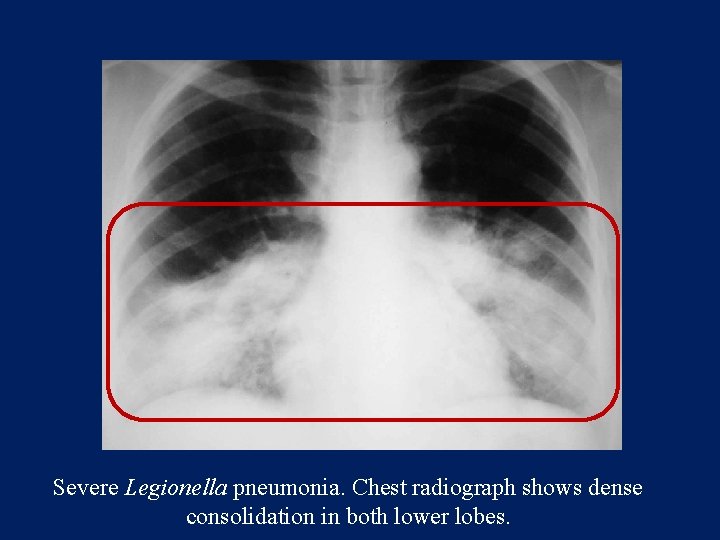

Radiology

Patchy reticular or reticulonodular opacities. Subsegmental and sometimes segmental atelectasis. Hilar adenopathy Pleural effusion

Severe Legionella pneumonia. Chest radiograph shows dense consolidation in both lower lobes.